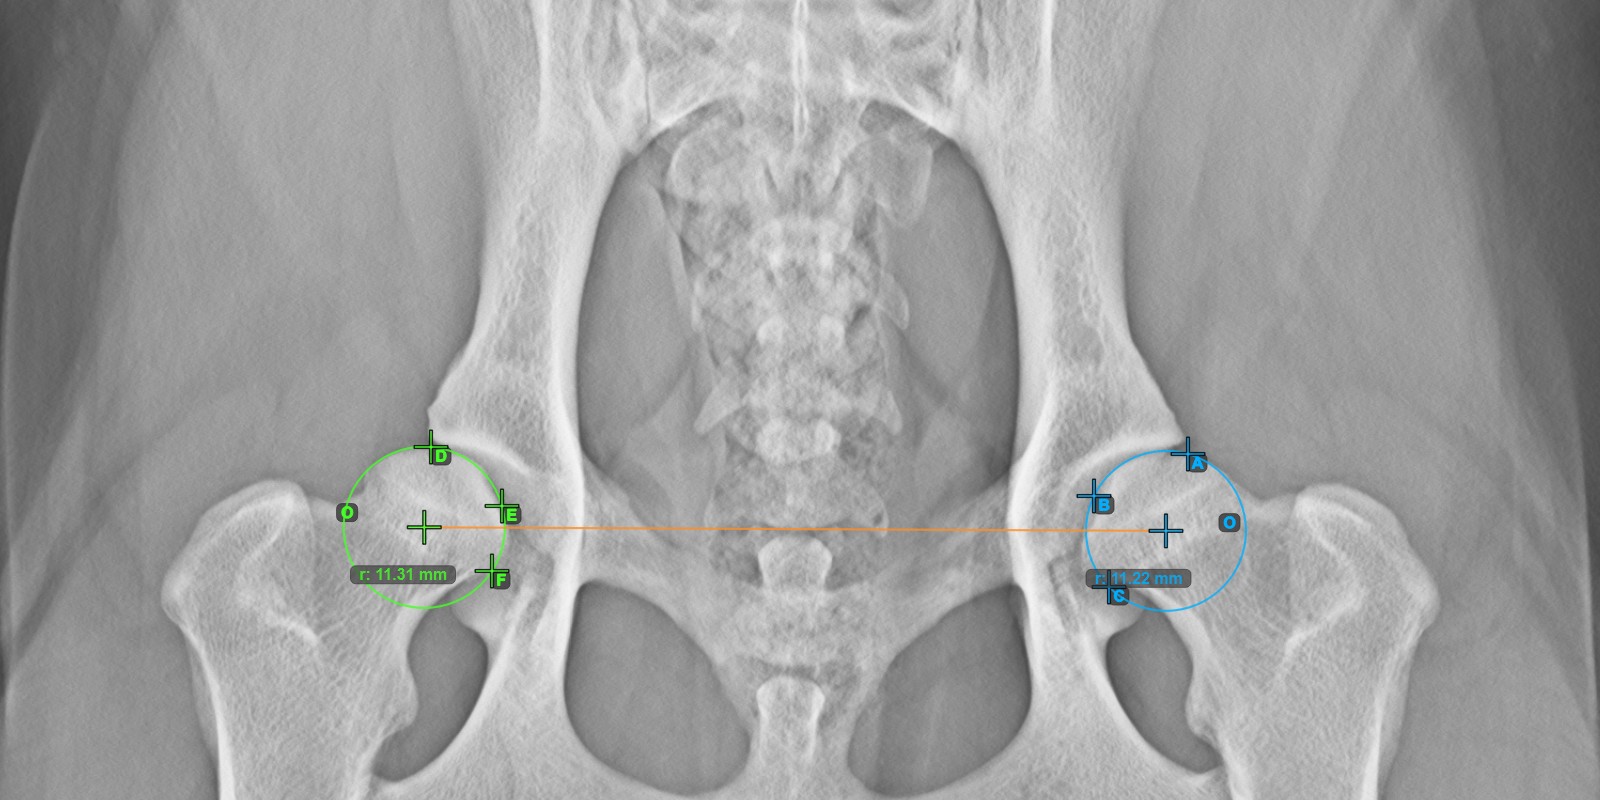

Fahren Sie fort, indem Sie die drei Punkte auf der Gelenkfläche des rechten Caput Femoris markieren.

Mark the three points on the articular surface of the right Caput Femoris (outside of the Fovea Capitilis). Regardless of the order, make sure to mark the most cranial point, the most caudal point and the midpoint of the femoral head. A circle will be automatically constructed based on the three placed poin

Das untenstehende Bild zeigt die typische Platzierung der drei Punkte auf der Gelenkfläche des rechten Caput Femoris.

../../_images/image100.jpg